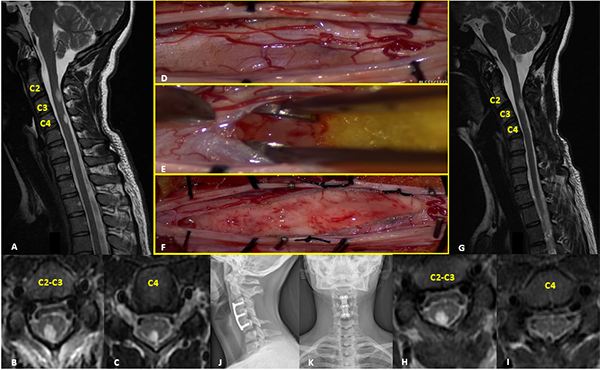

Paciente sexo femenino de 17 años con antecedente de trastornos de la conducta alimentaria que consulta por disestesias en palmas y plantas de un año de evolución, que progresa con debilidad en miembro superior izquierdo. Al examen físico se evidencia paresia leve braquial izquierda. La RM mostró dos lesiones focales hiperintensas en T2, localizadas en el cordón posterior derecho, que comprometen los niveles C2 y C3-C4 que no presentan realce tras la administración de contraste. Se realizó exéresis completa de lesión inferior y subtotal de la superior. El monitoreo neurofisiológico intraoperatorio no evidenció alteraciones significativas en los potenciales motores. En el postoperatorio inmediato la paciente recuperó la paresia del MSI. La RM control confirma remanente tumoral a nivel de C2 y resección total de la lesión C3-C4. La anatomía patológica informó astrocitoma pilocítico (Grado I de la OMS). La paciente evolucionó con inestabilidad cervical y cifosis progresiva requiriendo artrodesis cervical anterior (C3-C5) a los 7 meses de la cirugía (Figura 3).

Figura 3: Astrocitoma Pilocítico. A-C: RM prequirúrgica T2 cortes axiales y sagitales. D-F: Imágenes intraoperatoria pre y postresección. G-I: RM postquirúrgica T2 cortes axiales y sagitales. J-K: Radiografía cervical frente y perfil post-instrumentación.